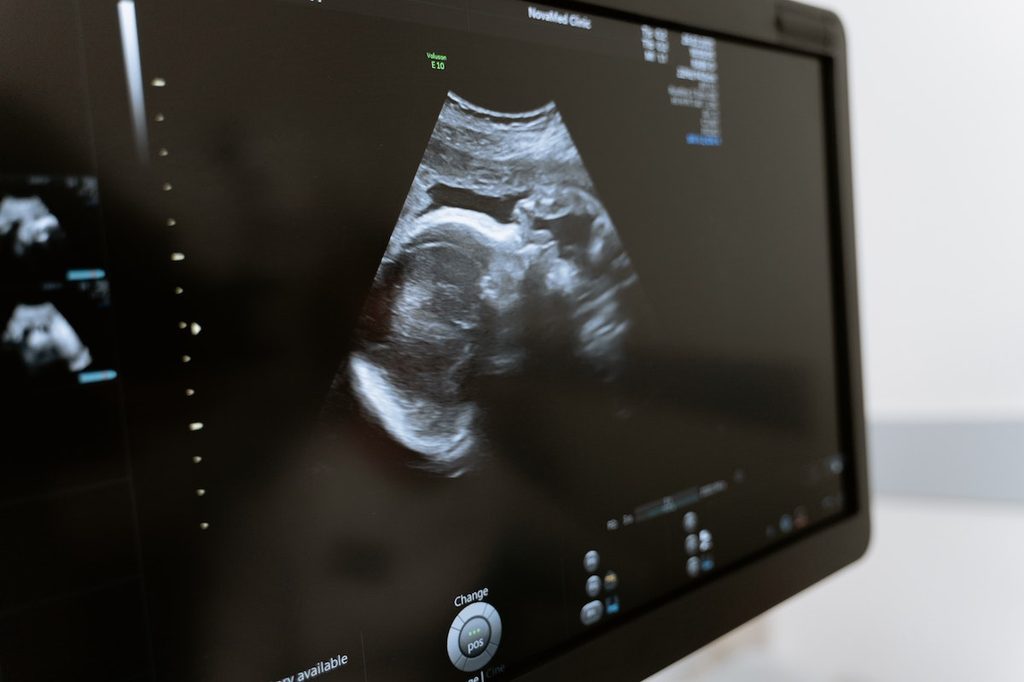

It’s amazing how quickly (but slowly) these soon-to-be humans develop. Your 8-week ultrasound may show a small blob-like photo, whereas an ultrasound done just a few weeks later will reveal a forming head and even cheekbones. As you progress in your pregnancy, you’ll see more and more development.

Doctors typically wait to do an ultrasound at 8 weeks pregnant because, even with modern technology, there’s not much to see in the early weeks of pregnancy. By seven to eight weeks, the ultrasound technician or doctor can see if the pregnancy is currently viable, rule out ectopic pregnancies (when the embryo implants in the fallopian tubes), and note a heartbeat — or heartbeats. You’ll learn whether you have a single or multiple pregnancy at your first ultrasound.

The fetus will usually look like a tiny blob with a tail or a seahorse, but that will change rapidly. This ultrasound is typically done transvaginally for a better picture.

At 12 weeks, the ultrasound technician or doctor can see the developing fetus through the abdominal wall. Expect to have some gooey gel placed on your stomach. Then, the tech will put a wand on your stomach. Take a look at the screen — you’ll see several new developments.

By 12 weeks, fetuses have a clearly developing head. You may even note your partner’s dimples (but you’ll need to wait a while to truly confirm that’s true). Ultrasounds at 12 weeks are exciting for another reason: They’re often the first time you hear the heartbeat — it’s music to your ears, especially if you’re nervous.